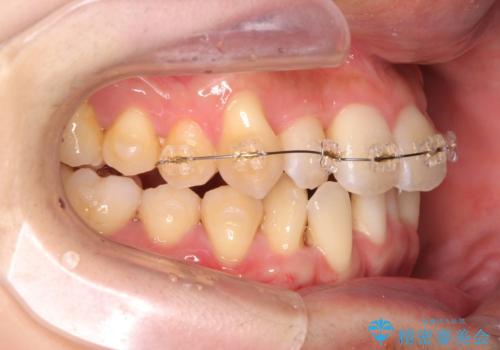

- インビザライン +部分ワイヤー矯正

4本の小臼歯抜歯を避け、下顎前歯の1本抜歯の極力少ない抜歯本数で審美的な歯並びを得る治療計画としました。

すれ違いを治すのが得意な前歯部の部分ワイヤーを用いることで、治療期間を短縮することができました。